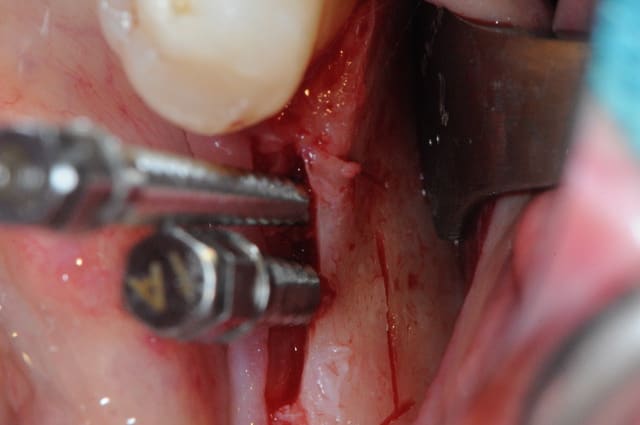

Cas 1-coté gauche maintenant:

photo:

1- ouverture, forme et configuration différente

2- une fois échauffée avec le coté droit, je me dis allez hop, j'attaque une expansion. donc incision crestale avec décharges osseuses

3- mise en place des expanseurs de Mesinger A et B

4-5 notez que l'incision de décharge étant oblique , elle sert également de garde fou contre une éventuelle fracture osseuse. l'os "mobile" vient buter contre l'os "immobile"

la suite en primeur pour ceux qui viennent à Sallanches les 28 et 29 Mars...